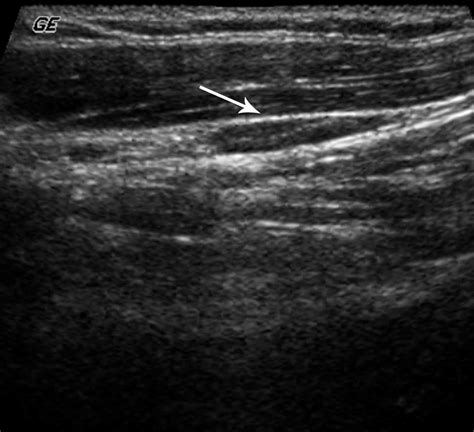

• Size and Shape: Normal nodes are typically oval, whereas malignant nodes may appear more rounded or spherical.

• Internal Architecture: Healthy nodes have a clear, bright central area called the “fatty hilum.” The absence of this hilum can be a warning sign.

• Border Definition: Clear, regular borders are generally reassuring, while irregular or “matted” borders may warrant biopsy.